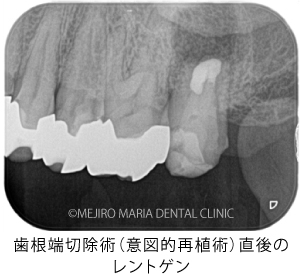

当院で精密根管治療を施しましたが、瘻孔(フィステル・サイナストラクト)を消失させることが難しく、追加処置として歯根端切除術(今回は意図的再植術)を行いました。また、術前に撮影したCT画像より、根尖性歯周炎が原因と考えられる上顎洞炎(蓄膿症/ちくのうしょう)の併発も確認できました。

歯根端切除術(意図的再植術)から3週間後の経過観察で、瘻孔の消失が確認できました。また、術後3ヶ月経つと、根尖部付近に確認できていた根尖性歯周炎も小さくなりました。患者様も「噛んだときにも、違和感や痛みなどはない」ということで、予後は良好だと判断しました。今後は最終補綴処置を行う予定です。